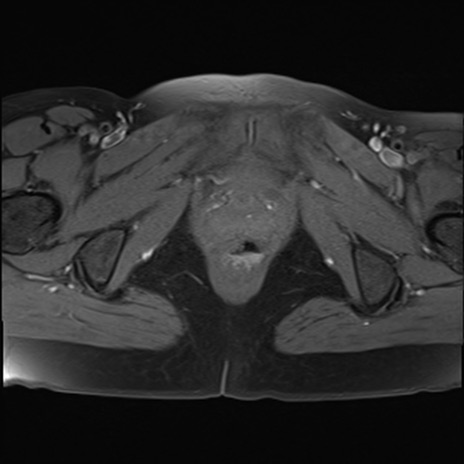

MRI(4日後)

DWI/ADC